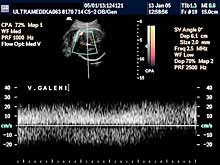

3. Arteriovenske malformacije su ispad prve faze embriogneze tj. histiogeneze. Ona započinje u toku 6-11 nedelje gestacije kada ne dolazi do formiranje moždanih kapilara. Rezultat ovoga je direktna komunikacija između cerebralnih (moždanih) arterija i dubokih drenažnih vena mozga. Ovakva situacija dovodi do direktnog šanta arterijske krvi u vene, naime "zaobilaze“ se neadekvatno formirani kapilari u mozgu. Iako je greška nastala rano, tek sa ukupnim povećanjem volumena mozga i količine krvi koja kroz njega prolazi a koja nastaje u III trimestru, moguće je ultrazvukom registrovati vene koje su postale značajno proširene i aneurizmatske. Jedna od najčešće prisutnih patoloških komunikacija je tok krvi u drenažnu venu Galen-i. Njeno aneurizmatsko proširenje može dovesti do kompresije na mozak koji zaostaje u rastu -postaje hipoplazičan i atrofičan a može doći i do formiranja hidrocefalusa.

Od stepena izostanka formiranja moždanih kapilara biće i izraženo ispoljavanje ove bolesti. Ako je ova greška moždane cirkulacije veća postoji smanjen otpor proticanja krvi kroz mozak i veći protok kroz leziju a samim tim se i veća količina krvi vraća u srce ploda. Ovakva situacija može dovesti do srčane isuficijencije još u toku trudnoće, a obavezno se javlja nakon rađanja deteta. Krajnji rezultat je obično nepovoljan za plod.

A) Savremena dijagnostika korišćenjem Broad band kolor Dopplera (Broad band-CD) i kolor Power Dopplera (CPD) bez obzira na količinu krvi koja prolazi kroz vaskularnu anomaliju i bez obzira pod kojim uglom je moguće poslati ultrazvučni talas, je u stanju da postavi dijagnozu ove ozbiljne vaskularne malformacije CNS. U nepovoljnim uslovima standardna ultrazvučna tehnika sa CD nije u stanju da prikaže ni normalne krvne sudove Wilisovog šestougla niti duboke drenažne vene . Jedino savremena ultrazvučna tehnika je u stanju da postavi dijagnozu bez obzira na položaj ploda koji obično bitno ne menja svoju poziciju u toku pregleda u III trimestru trudnoće. Takođe CPD tehnika je u stanju da proceni tačno hemodinamiku moždane i srčane cirkulacije i da tačnu prognozu. Ovo je važno jer se neke aneurizme vene Galen-i mogu lečiti nakon rađanja deteta embolizacijom krvnih sudova.